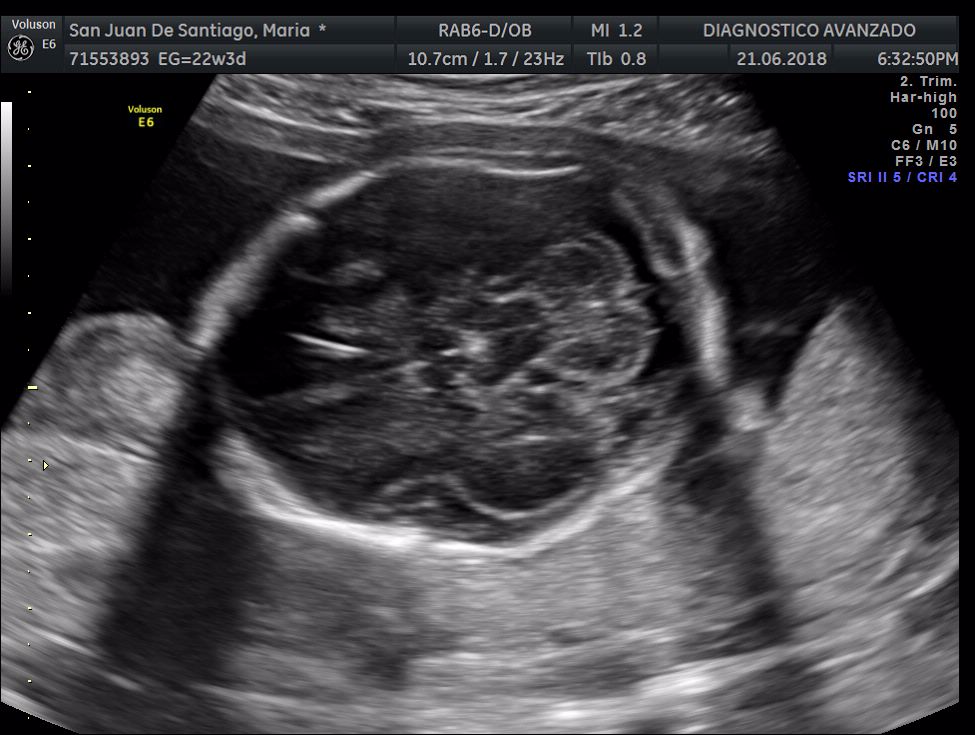

¡Hola a todos! Hoy hemos ido a hacer la tradicional ecografía 3D de la niña, os dejamos todo el material (aunque es un poco demasiado).